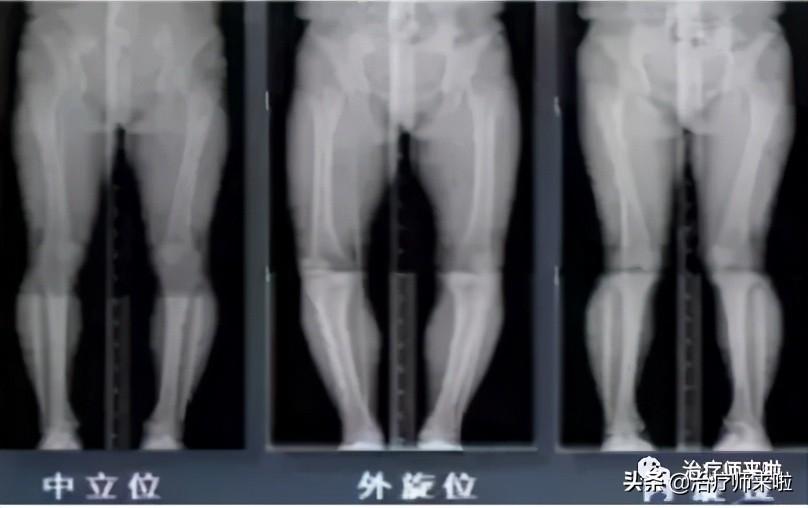

六、诊断方法

1、影像学检查:X线检查,如上图所示